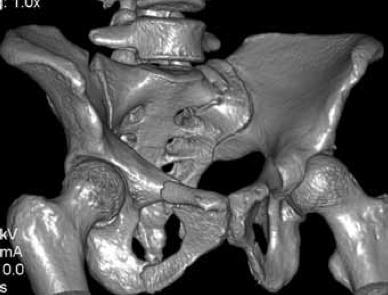

Клинический пример. Пациентка М., 21 год, поступила в клинику через 1,5 месяца после ДТП с диагнозом: ротационно-нестабильное повреждение таза; U-образный перелом крестца с вершиной над SII. Оскольчатый перелом крыла правой подвздошной кости с частичным повреждением правого крестцово-подвздошного сочленения. Радикулопатия S1 справа, S2, S3 с обеих сторон средней степени (Фиг. 1 - обзорная рентгенограмма таза (а); КТ сканы в сагиттальной (б) и горизонтальной (в) плоскости при поступлении).

По предлагаемому способу в одну операционную сессию выполнен:

- остеосинтез крыла подвздошной кости винтами и фиксация U-образного перелома крестца илиосакральным винтом для стабилизации повреждений тазовых костей;

- костнопластическая остеотомия задней стенки крестцового канала, открытая декомпрессия дурального мешка, ремоделирование крестцового канала;

- фиксация ламинектомированного фрагмента по линии остеотомии сетчатой пластиной (Фиг. 2 - представлена обзорная рентгенограмма таза (а) и КТ сканы в сагиттальной (б) и горизонтальной (в) плоскости после операции. После операции пациентка активизирована на третьи сутки, рана заживлена первичным натяжением, швы сняты не 12 сутки. Проводилась медикаментозная и электоронейростимуляция. Выписана из стационара на 17 сутки после операции.

На контрольном осмотре через 1 месяц после операции пациентка жалоб не предъявляла. Достигнуты: полный регресс неврологической симптоматики, консолидация переломов костей таза. Получен хороший функциональный результат.